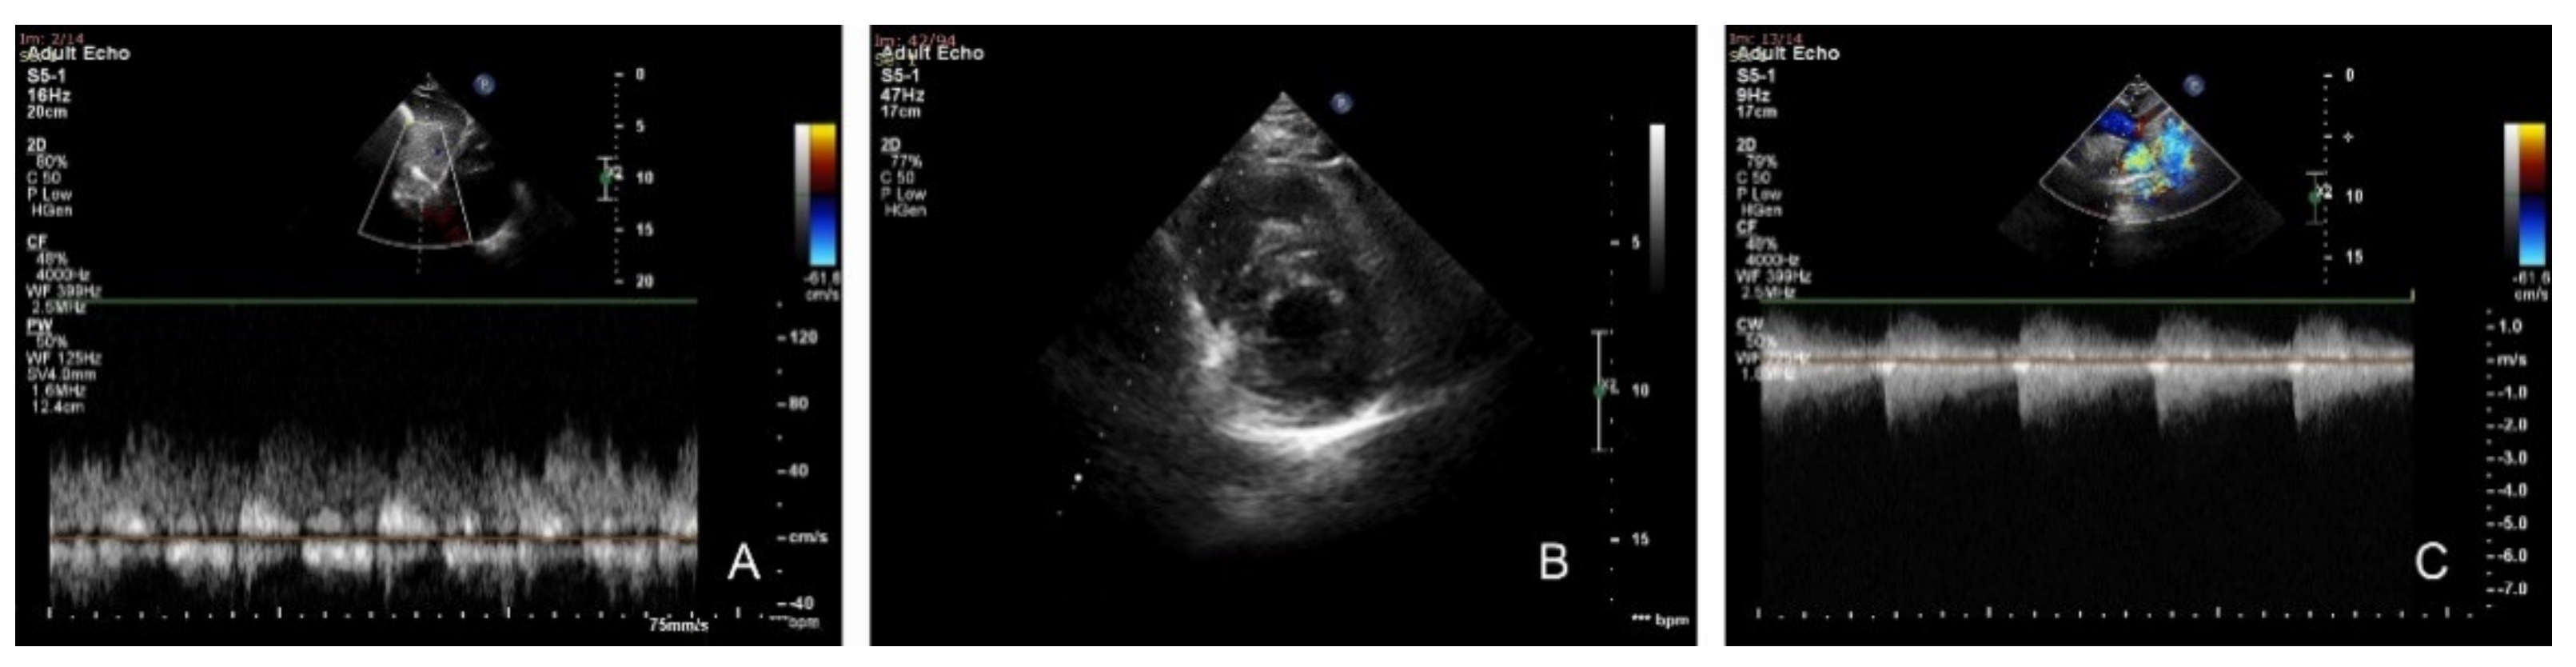

2.2. Diagnostic Criteria

2.3. Therapeutic Approach, Postprocedural Evolution, Cardiologic Follow Up